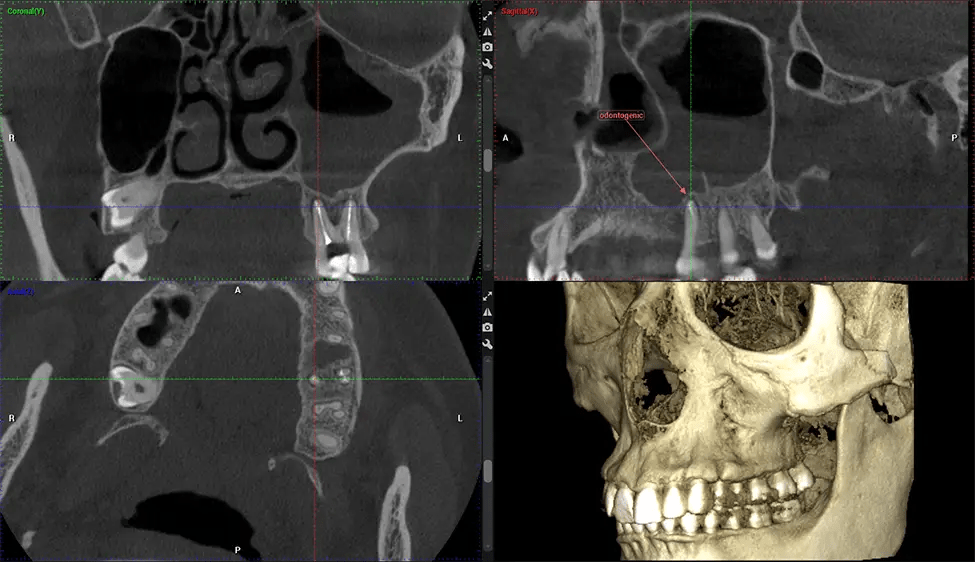

Cone Beam Computed Tomography (CBCT) is an advanced imaging technique used in dentistry and maxillofacial surgery to obtain detailed 3D images of the oral and maxillofacial structures. At Dr G Dental Studio, our CBCT scanners utilize a cone-shaped X-ray beam and a specialized detector to capture images from different angles. A computer then combines these images to create a 3D representation of the patient’s oral anatomy.

This 3D scan, called cone beam computed tomography, gives your dentist a more complete image of your oral anatomy and disease processes than a traditional X-ray. Unlike conventional X-rays, which capture a 2D image of your mouth from various angles, a 3D scan takes multiple digital X-rays for one image. It provides a complete view of your jaw, teeth, nerves, and soft tissues. This enhanced view allows dentists to detect minor issues not visible in traditional 2D scans, such as impacted wisdom teeth or bone fractures in the sinus cavity.

There are many benefits to using CBCT technology, especially compared to the traditional 2D X-ray format. One of the most significant advantages of CBCT scans is that they provide much more information than traditional X-rays. A scan lets your dentist see images from all angles of your jaw and mouth, including your sinuses, nasal cavity, cheekbones, and other surrounding areas. This added information helps your dentist craft a comprehensive treatment plan that addresses all aspects of your oral health.

Another significant benefit is that 3D imaging provides more precise images of your bone structure. These images are more detailed, providing you with a more accurate diagnosis. An accurate diagnosis means better treatment for you.

Oral and Maxillofacial Surgeon Complex oral surgeries, orthognathic (jaw) surgery, and removal of impacted teeth. Offers precise, three-dimensional visualization of the skull, jaw, and craniocervical junction to enhance diagnostic accuracy and minimize surgical risks.